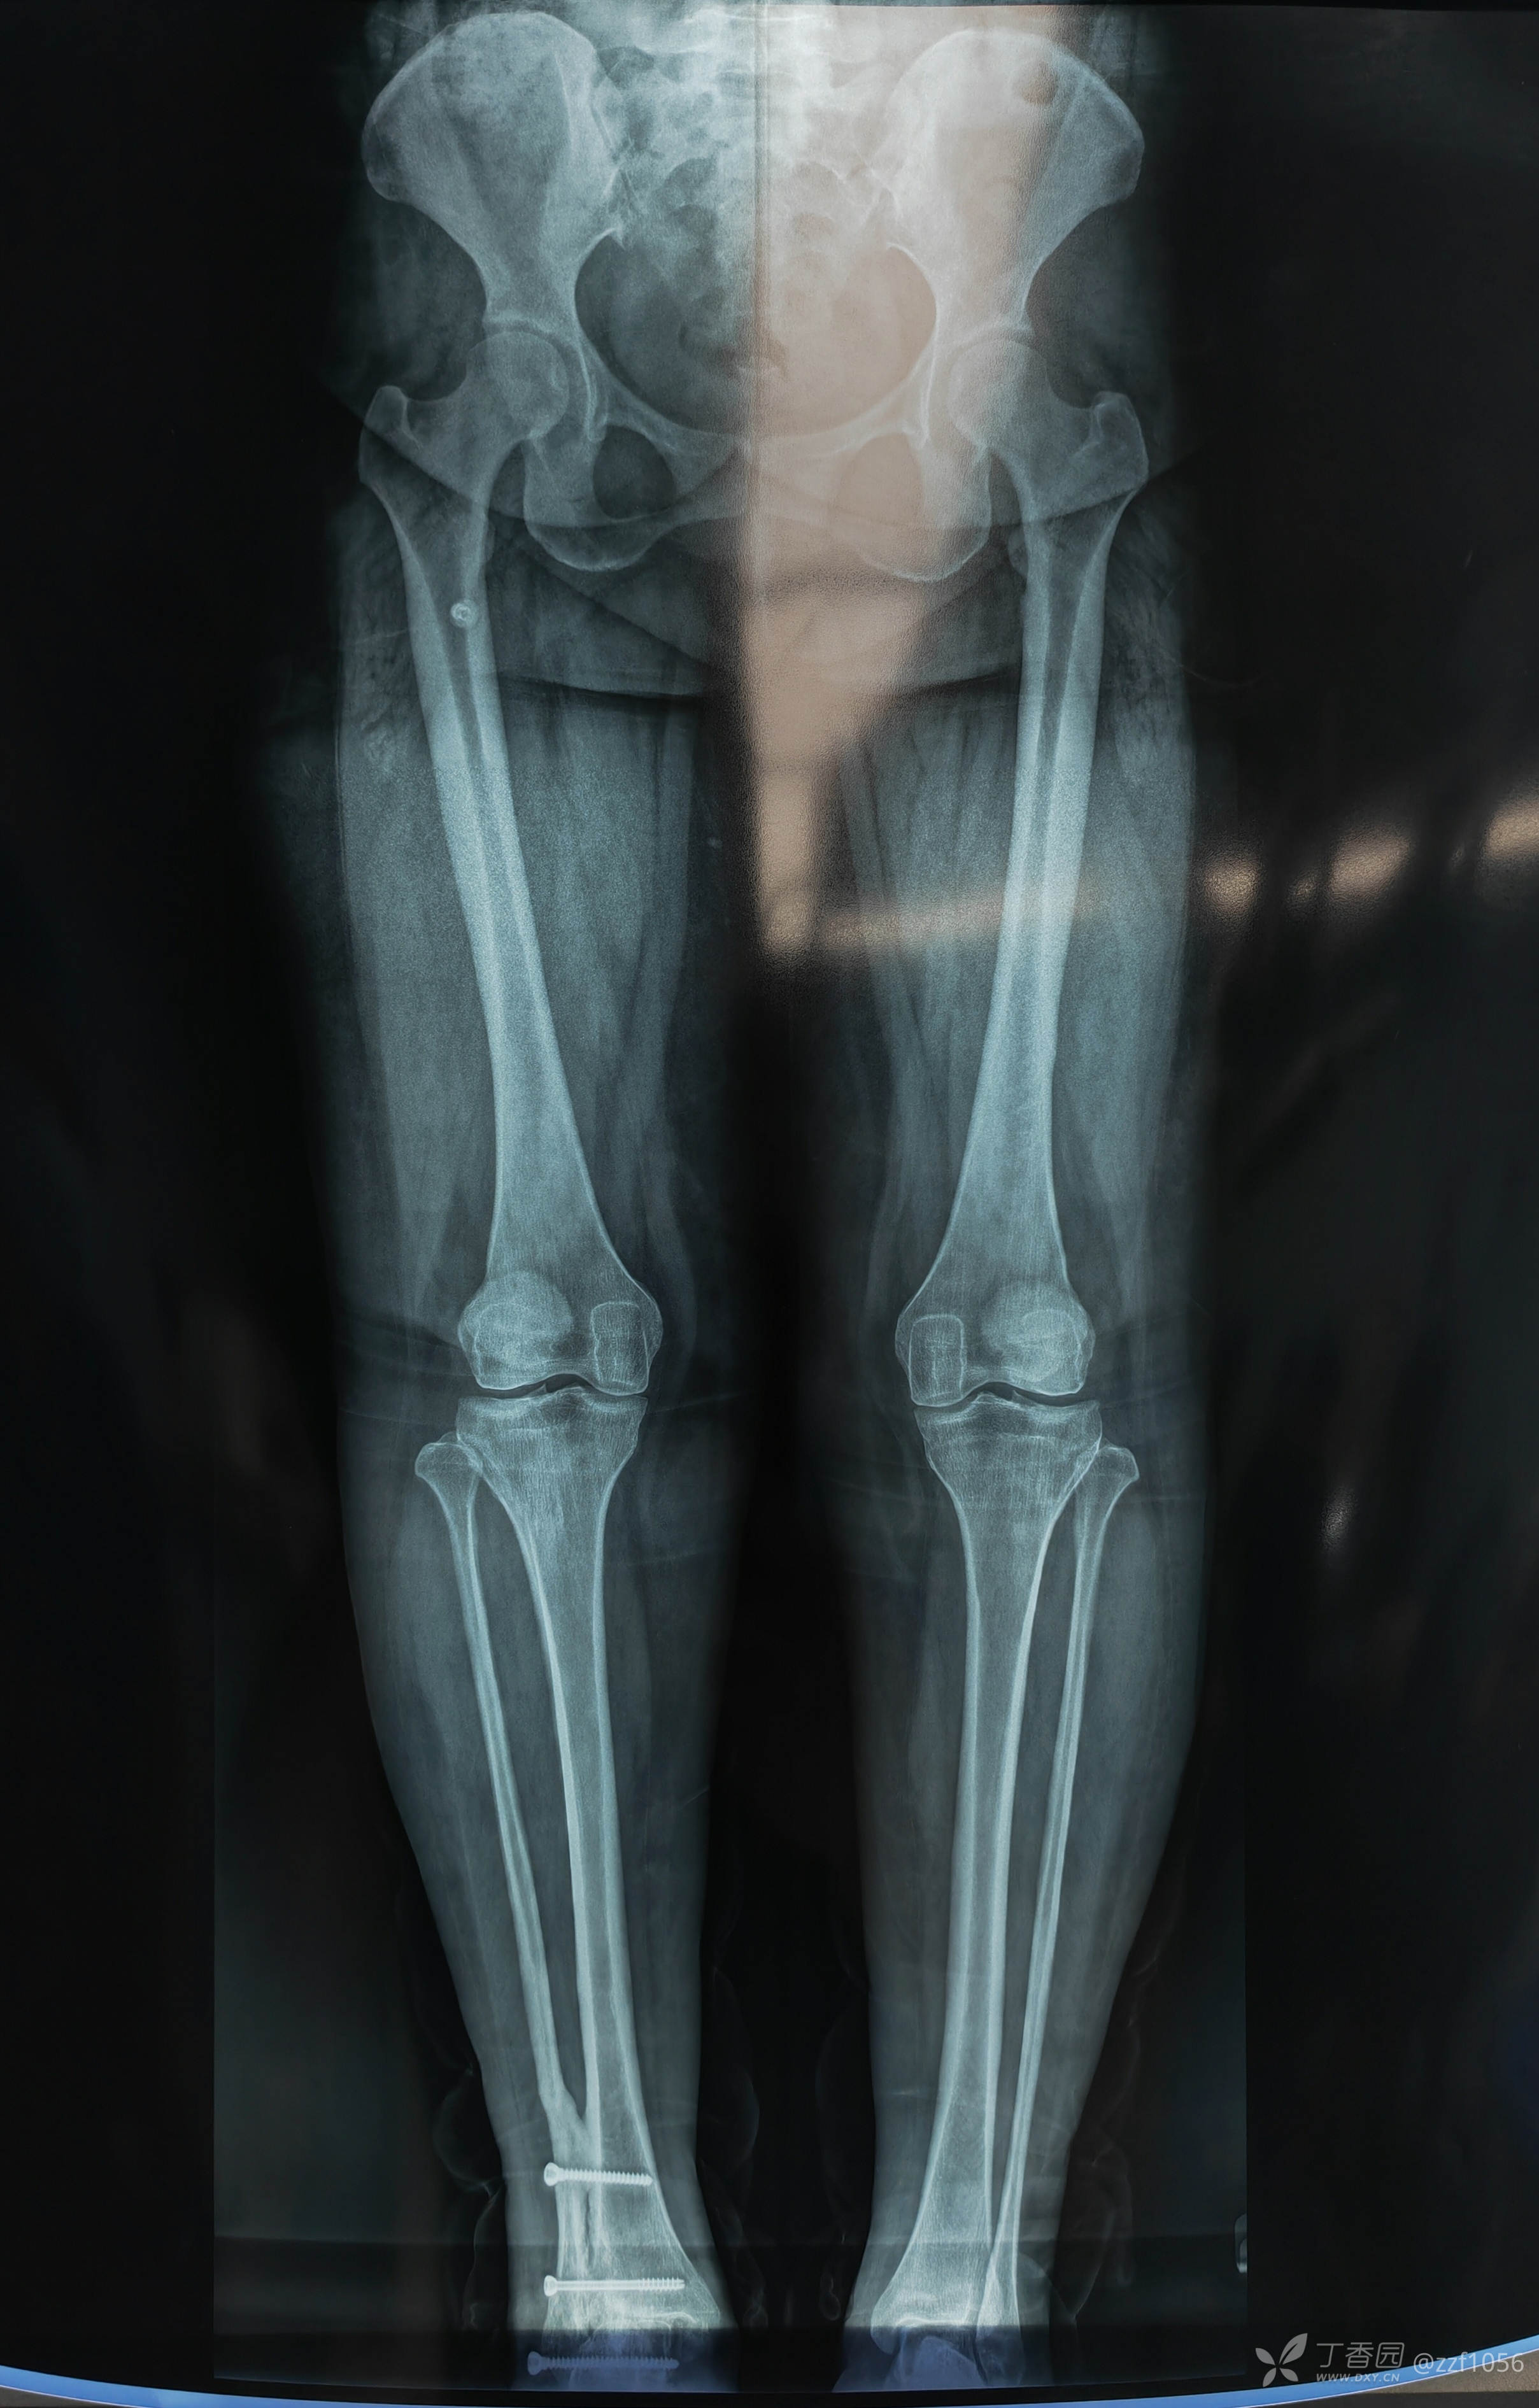

正位片力线

最近做了一例劈木机损伤,给患者看了一下照片,患者老公信誓旦旦说:当时骨折就是这个样式。